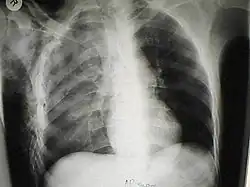

| A chest X-ray of a right sided pulmonary contusion associated with flail chest and subcutaneous emphysema | |